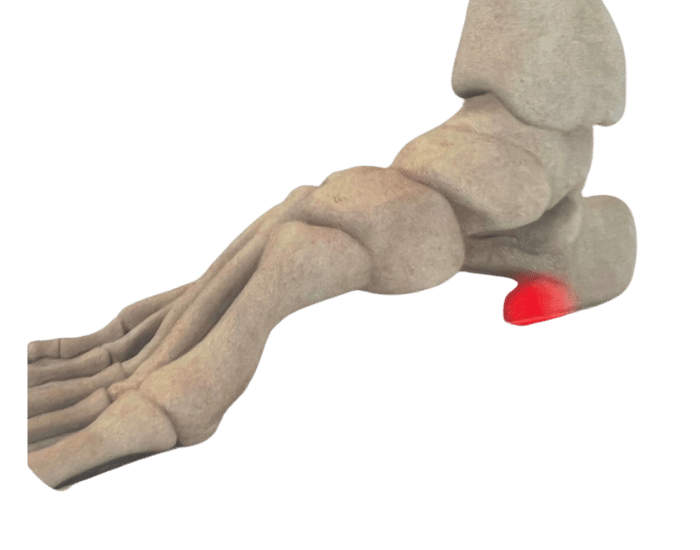

There are numerous reasons why you might need Custom Foot Orthotics. If you have pain in your foot, heel, knee or hip, have high arches or flat feet; or just being regularly on your feet and are getting any aches or pains in the feet or legs, or suffering from general foot pain while walking, running, playing sports or even at rest you qualify for Custom Foot Orthotics.